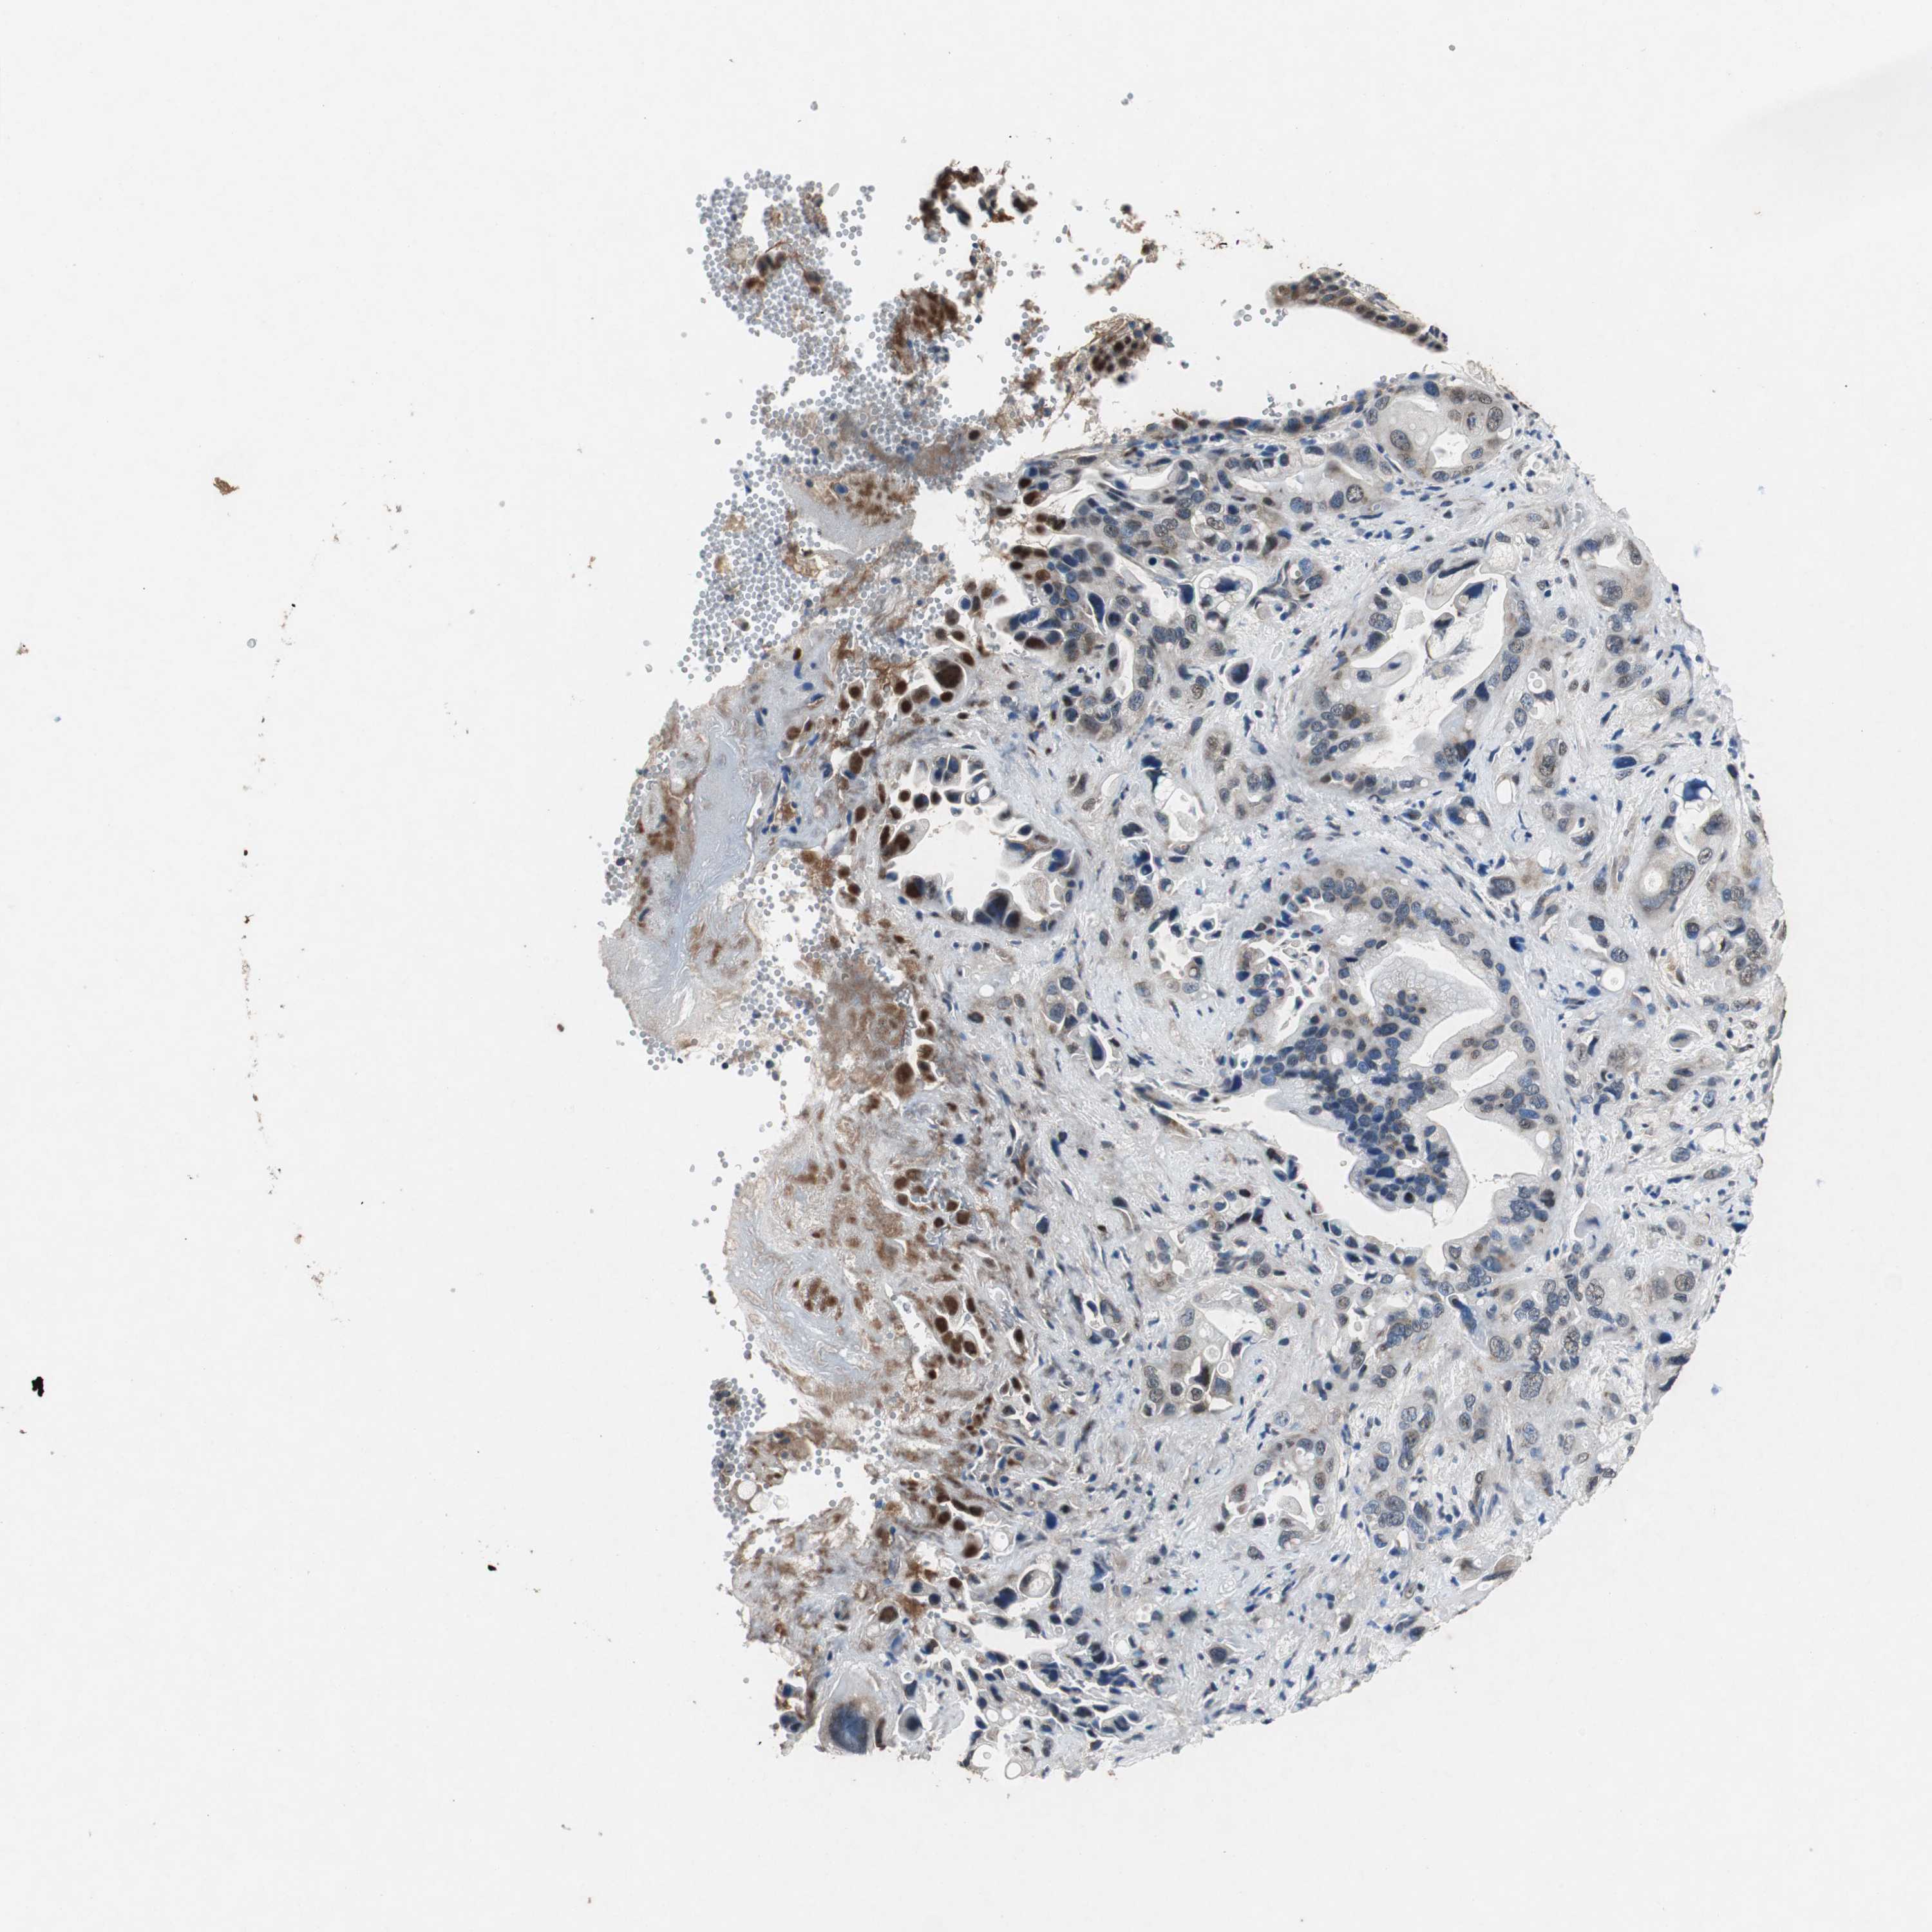

PANCREATIC CANCER - Protein expressioni

A mouse-over function shows sample information and annotation data. Click on an image to view it in a full screen mode. Samples can be filtered based on level of antibody staining by selecting one or several of the following categories: high, medium, low and not detected. The assay and annotation is described here.

Note that samples used for immunohistochemistry by the Human Protein Atlas do not correspond to samples in the TCGA dataset.

Antibody stainingi

Antibody staining in the annotated cell types in the current human tissue is reported as not detected, low, medium, or high, based on conventional immunohistochemistry profiling in selected tissues. This score is based on the combination of the staining intensity and fraction of stained cells.

Each image is clickable and will lead to virtual microscopy that enables deeper exploration of all samples and also displays staining intensity scores, fraction scores and subcellular localization as well as patient and tissue information for each sample.

Antibody HPA006047

Staining

High

Medium

Low

Not detected

Intensity

Strong

Moderate

Weak

Negative

Quantity

>75%

75%-25%

<25%

None

Location

Nuclear

Cytoplasmic/membranous

Cytoplasmic/membranous,nuclear

Adenocarcinoma, NOS

Adenocarcinoma, metastatic, NOS